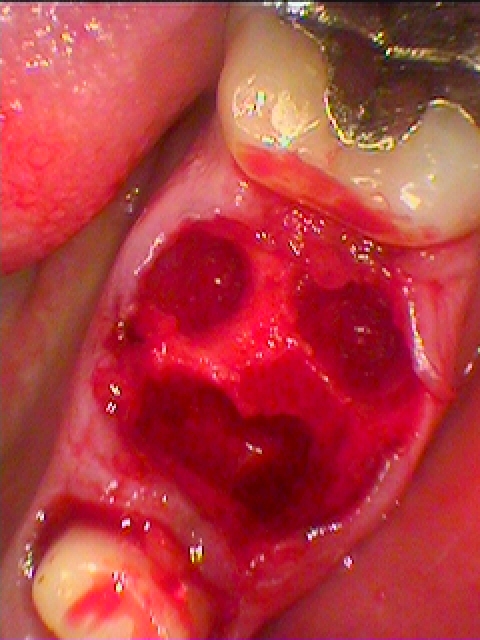

抜歯即時インプラント埋入を行っています

骨補填材を詰めています